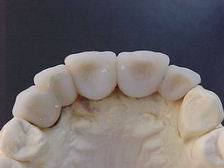

Munhões personalizados

Prótese metalocerâmica personalizada

Munhões personalizados sobre modelo VISTA OCLUSAL

Prótese metalocerâmica personalizada VISTA OCLUSAL